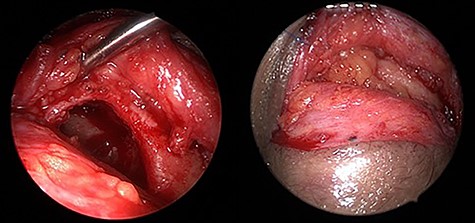

TOEA was selected after consulting the oculoplastic surgeon due to the lateral location of the frontal mucocele in addition to being an isolated mucocele with frontal sinus outflow obstruction. The frontal mucocele was successfully removed using TOEA through superior lid crease (SLC) incision followed by orbicularis oculi dissection, which exposed the orbital septum. The dissection until the superior orbital rim was exposed. The periosteum of the orbital rim was incised and peeled off, which exposed a bulging mass medially. The mass with surrounding fibrosis was excised completely and sent for histopathological evaluation. A bony defect was revealed at the lower aspect of the left frontal sinus measuring around 1.5 × 2.0 cm (Fig. 4). The left frontal sinus cavity was visualized completely through the bony defect using a combination of 0-degree and angled endoscopes. This revealed an isolated frontal sinus cavity with a completely obstructed frontal sinus drainage pathway medially, as a result of the previous head trauma sustained 40 years ago. Then, the frontal sinus mucosa was peeled off entirely from the bone using angled curettes followed by complete obliteration of the frontal sinus cavity using s fat graft harvested from a small incision on the left periumbilical area (Fig. 5). The periosteum of the orbital rim and the skin incision were closed using multiple 5-0 Vicryl and 6-0 Vicryl Rapide sutures, respectively. The patient made an uneventful postoperative recovery and was discharged on the following day of the surgery in a stable condition.

Endoscopic transorbital view of the isolated left frontal sinus cavity after completely peeling off the frontal sinus mucosa (a) and after fat obliteration of the cavity (b).